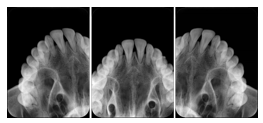

3. A dental provider wishes to capture a series of DICOM IO images for the patient’s dentition. The tooth morphology, teeth are divided into molars, premolars, canines and incisors, and a number of images for each jaw. The anatomic information was captured utilizing the triplet of schema. This standard code sequence is based on ISO 3950-2010, Dentistry - Designation system for teeth and areas of the oral cavity.

Every IO image should have anatomic information either through the primary or modifier sequence.

In most standard cases, images are oriented in structured layouts. These structured displays are useful to be shared between providers for reference purposes.

Table OO.1.1-1 shows structured display standard templates, where Viewset ID is based on the Japanese Society for Oral and Maxillofacial Radiology (JSOMR) classification provided by JIRA (Japan Medical Imaging and Radiological Systems Industries Association, www.jira-net.or.jp). Expected or typical teeth to be imaged location, region and designation codes are based on ISO 3950-2010, Dentistry - Designation system for teeth and areas of the oral cavity. For all the hanging protocols listed in OO.1.1-1, the value to use for Hanging Protocol Creator (0072,0008) is "JSOMR" and the value to use for Hanging Protocol Name (0072,0002) does not include "JSOMR" (e.g., "DL-S001A", not "JSOMR DL-S001A").